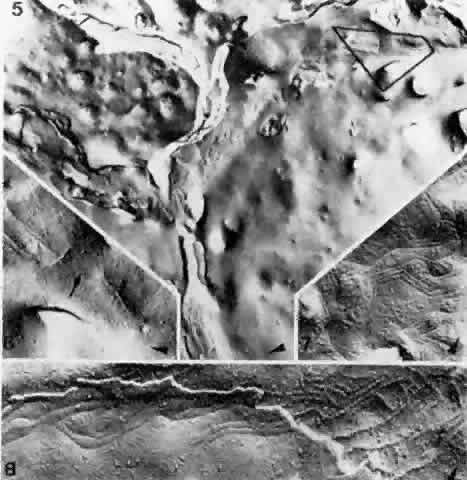

Fig. 28. Composite of fracture faces of zonulae occludentes between endothelial

cells of a choroidal venule. Extensive zonulae occludentes (5) in center. In most places the strands are branching and interconnected; in

limited areas they are entirely missing. Higher magnification (6) of delineated area of 5 with interruption (arrow) of the zonula occludens (× 46,000). Typically angulated strands

of a zonula occludens (7), seen as imprinted grooves on cell surface (× 42,000). Zonula occludens (8) with cleavage plane jumping from one endothelial cell to another, exposing

grooves on cell surface on left and ridges on cell at right (× 54,000). Arrowheads

in all figures indicate the direction of platinum-carbon

shadowing. (Spitznas M, Reale E: Fracture faces of fenestrations and junctions of

endothelial cells in human choroidal vessels. Invest Ophthalmol Vis Sci 14:98, 1975) Fig. 28. Composite of fracture faces of zonulae occludentes between endothelial

cells of a choroidal venule. Extensive zonulae occludentes (5) in center. In most places the strands are branching and interconnected; in

limited areas they are entirely missing. Higher magnification (6) of delineated area of 5 with interruption (arrow) of the zonula occludens (× 46,000). Typically angulated strands

of a zonula occludens (7), seen as imprinted grooves on cell surface (× 42,000). Zonula occludens (8) with cleavage plane jumping from one endothelial cell to another, exposing

grooves on cell surface on left and ridges on cell at right (× 54,000). Arrowheads

in all figures indicate the direction of platinum-carbon

shadowing. (Spitznas M, Reale E: Fracture faces of fenestrations and junctions of

endothelial cells in human choroidal vessels. Invest Ophthalmol Vis Sci 14:98, 1975)